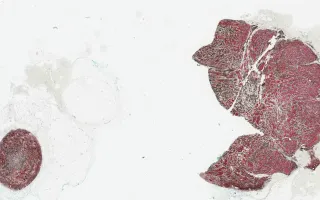

The incisional biopsy demonstrates a multinodular proliferation of densely pigmented melanocytes within the dermis. The bleached H&E slide reveals nuclear atypia and 2 mitoses per mm². The overlying superficial dermis and epidermis are uninvolved. This lesion likely represents a primary dermal melanoma with a blue nevus-like morphology. Alternatively, it may represent a melanoma in which the superficial and radial growth patterns have not been sampled.

The immunohistochemistry shows lesional cells to be positive for HMB45 and Melan-A.

This slide shows Melan-A stain, see related content for H&E, HMB45, and bleached H&E stains.